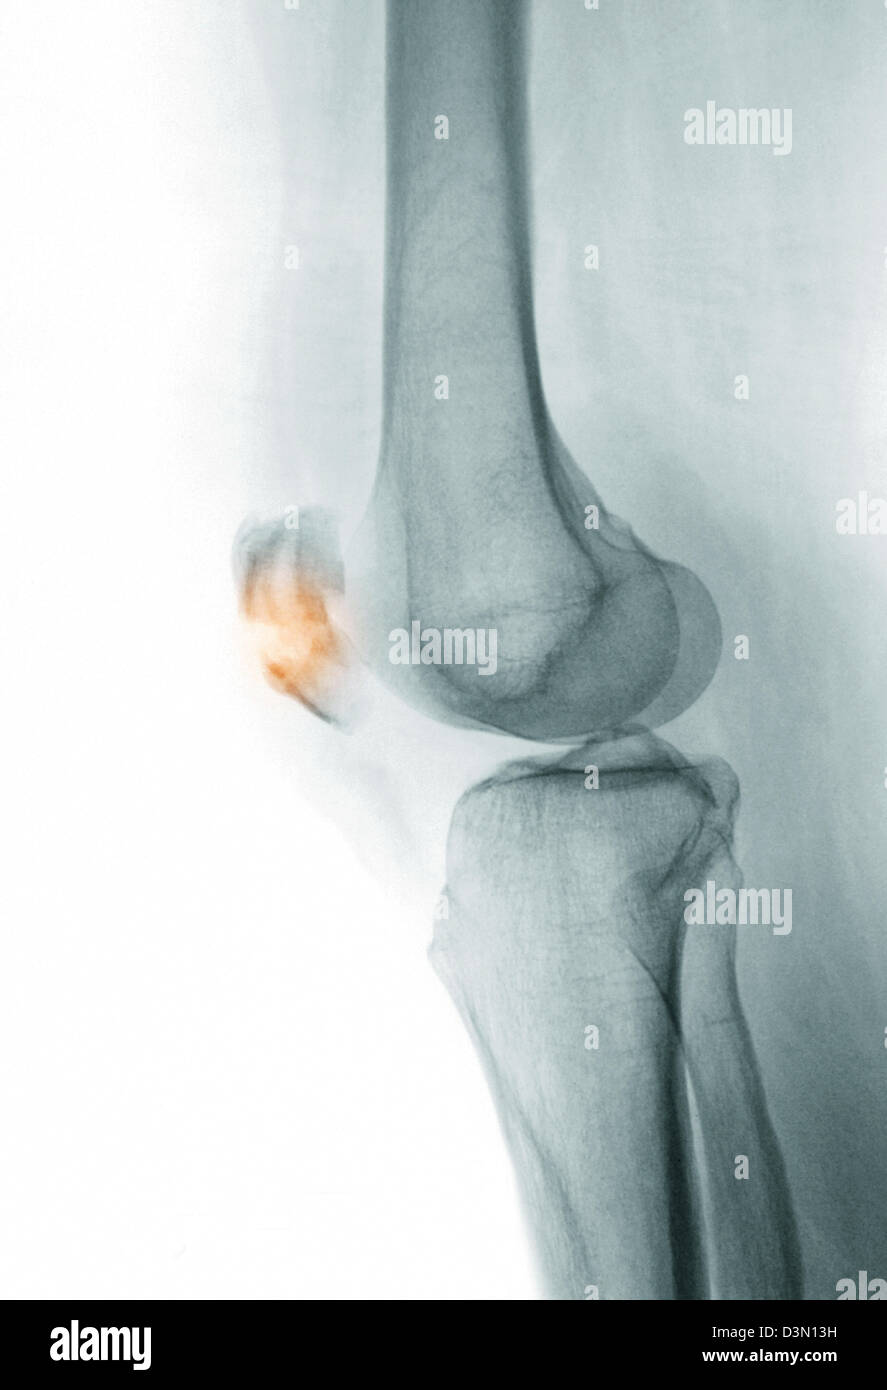

Rottura della rotula. Quando questo stress è traumatico, e di là di quanto l’osso in grado di sopportare, può verificarsi una rottura della rotula con conseguente frattura Rappresenta l’1% di tutte le fratture del corpo umano, ed più frequente negli uomini La frattura di rotula può essere di varia entità e danno. La frattura della rotula è una problematica che colpisce il ginocchio ed è riscontrata frequentemente in ambito ortopedico, rappresentando circa il 60% delle fratture che interessano il ginocchio Queste sono delle lesioni estremamente invalidanti per il soggetto che le subisce poiché compromettono il meccanismo di estensione dell’arto inferiore, funzione indispensabile in tutti i. La fractura de rótula, también llamada fractura patelar, es la rotura o pérdida de continuidad ósea del hueso rotulianoAl encontrarse este hueso en la parte anterior de la rodilla es más propenso al golpe La mayoría de estas fracturas ocurren como resultado de traumatismos por accidente de tránsito o caída.

• Fratture della rotula • Rottura di molte fibre • Dolore acuto • Arresto dello sforzo, zoppia • Recupero in 46 settimane La rottura • Rottura di molti fasci • Dolore acuto • Impotenza completa • Infossamento precoce • Recupero in più di 3 mesi. L’articolazione del ginocchio è composta da tre ossa femore, tibia e rotula Quest’ultima, a causa della sua collocazione, è quella che corre un maggior rischio di frattura in caso di trauma Un infortunio serio che può limitare se non impedire i movimenti Che caratteristiche ha la frattura della rotula e come si interviene in sua. Berkeley Electronic Press Selected Works.

La frattura della rotula è un evento che si verifica quasi esclusivamente in seguito a un trauma diretto Questo perché la rotula è la zona del ginocchio più esposta verso l’esterno Delle tre ossa che formano il ginocchio, che sono la tibia, il femore e la rotula, quest’ultima è facilmente e direttamente palpabile anche dai non espertiNelle cadute dalle scale l’impatto è sempre. Gentilissimo dottore, a mia moglie, a causa di una caduta, è stata riscontrata la frattura pluriframmentaria scomposta della rotula con diastasi fra i 2 frammenti di circa 3,2 centimetri, vorrei. Sintomi, con la rottura della cartilagine, e tali movimenti Precedenti infortuni al ginocchio come una distorsione o una lussazione della rotula con conseguente rottura di uno dei Artrosi ginocchio sintomi e terapie utili L artrosi al ginocchio pu essere trattata con diverse tipologie d intervento.

È la rottura della rotula e solitamente avviene per un trauma diretto tra la rotula e una superficie dura Le situazioni a cui può essere dovuta sono la caduta;. Le malattie che interessano la rotula variano, partendo dalla lussazione e arrivando alla rottura dei legamenti e i tendini collegati alla rotula In molti casi ricorrere al centramento della rotula con l’ausilio di un tutore può correggere o alleviare il problema, ma anche prevenirlo se necessario. Altrettanto raramente può verificarsi una frattura della rotula da stress associato ad un aumento del volume di salto Anche una lussazione può tuttavia comportare una frattura della rotula, in particolar modo se forzata Sintomi Il tipico sintomo in presenza di frattura della rotula è il dolore al livello del ginocchio.

Il test di sollevamento della gamba tesa può rivelare la rottura del meccanismo estensore, che include il tendine del quadricipite, la rotula e il tendine rotuleo Imaging e laboratori Una radiografia è spesso il primo test di imaging utilizzato, in quanto può mostrare se è presente una frattura, che è importante individuare o escludere. • Fratture della rotula • Rottura di molte fibre • Dolore acuto • Arresto dello sforzo, zoppia • Recupero in 46 settimane La rottura • Rottura di molti fasci • Dolore acuto • Impotenza completa • Infossamento precoce • Recupero in più di 3 mesi. Malattie della Rotula Le più note problematiche che possono interessare la rotula sono la lussazione (o dislocazione), la rottura del tendine rotuleo e la frattura LUSSAZIONE DELLA ROTULA La lussazione della rotula, o dislocazione patellare, è quando la rotula scivola fuori dalla sua normale posizione.

Anatomia della rotula La rotula o patella è un osso sesamoide corto, tozzo e massiccio a forma di castagna con la base superiore e l'apice inferiore Il suo margine superiore da inserzione al tendine del quadricipite femorale che si prolunga in un tendine robusto che a sua volta decorre dall'apice inferiore della rotula fino alla tuberosità. Il test di sollevamento della gamba tesa può rivelare la rottura del meccanismo estensore, che include il tendine del quadricipite, la rotula e il tendine rotuleo Imaging e laboratori Una radiografia è spesso il primo test di imaging utilizzato, in quanto può mostrare se è presente una frattura, che è importante individuare o escludere. A settembre sono caduta e rotta la rotula destra, operata e due trasfusioni un po’ anemica con beta talassemia Tra tre mesi dovrei rimuovere tutto e necessario?.

Fratture della rotula In caso di frattura della rotula si avranno dolore, impossibilità di piegare il ginocchio, ecchimosi Talvolta è imposibile ridurre o curare la frattura della rotula mediante l’applicazione d’una fasciatura elastica o di una ginocchiera gessata seguita dopo circa quindici giorni di massaggi. A settembre sono caduta e rotta la rotula destra, operata e due trasfusioni un po’ anemica con beta talassemia Tra tre mesi dovrei rimuovere tutto e necessario?. Leggi la voce ROTULA sul Dizionario della Salute ROTULA definizione, ultime notizie, immagini e video dal dizionario medico del Corriere della Sera.

Colpi di arti marziali finiti male;. La frattura della rotula provoca una grave limitazione del movimento del ginocchio perché il dolore si sente anche quando si cammina La rottura della patella rappresenta circa l’1% di tutte le fratture e oltre la metà di quelle del ginocchio I fattori che predispongono a questo tipo di frattura sono Osteoporosi;. Complicanze intervento?riprendere come prima ?.

Si segnalano Chris Brunt per l'Irlanda del Nord, che salterà l'europeo a causa di un infortunio al legamento crociato rimediato il primo per una rottura della rotula, il secondo per un problema agli adduttori ed il terzo per una lesione del crociato il terzo per la rottura del legamento crociato anteriore del ginocchio destro e l'altro. Le fratture della rotula possono essere causate da forze indirette o da un traumaNel primo caso è comune che il quadricipite rompa la rotula quando si contrae nel tentativo di estendere un ginocchio forzatamente flesso;. FRATTURA ROTULA 4,00% FRATTURA TIBIA DIAFISARIA 3,00% ASPORTAZIONE CHIRURGICA DI PARTE DI TECA CRANICA (indipendentemente dall’estensione della breccia) 8,00% ROTTURA MILZA CON SPLENECTOMIA 10,00% ROTTURA RENE CON NEFRECTOMIA 15,00% ESITI EPATECTOMIA (oltre un terzo del parenchima) 10,00%.